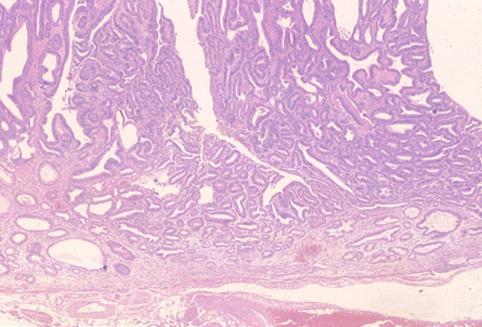

질환(병리주체)의 분류 악성 상피성종양/선암

부위(장기별) 위(부위)/전정

검사방법 마이크로

종양의 육안분류 0형(표재형)/I형(I)

종양의 최대경(밀리미터) 15~19

종양의 심달도 m